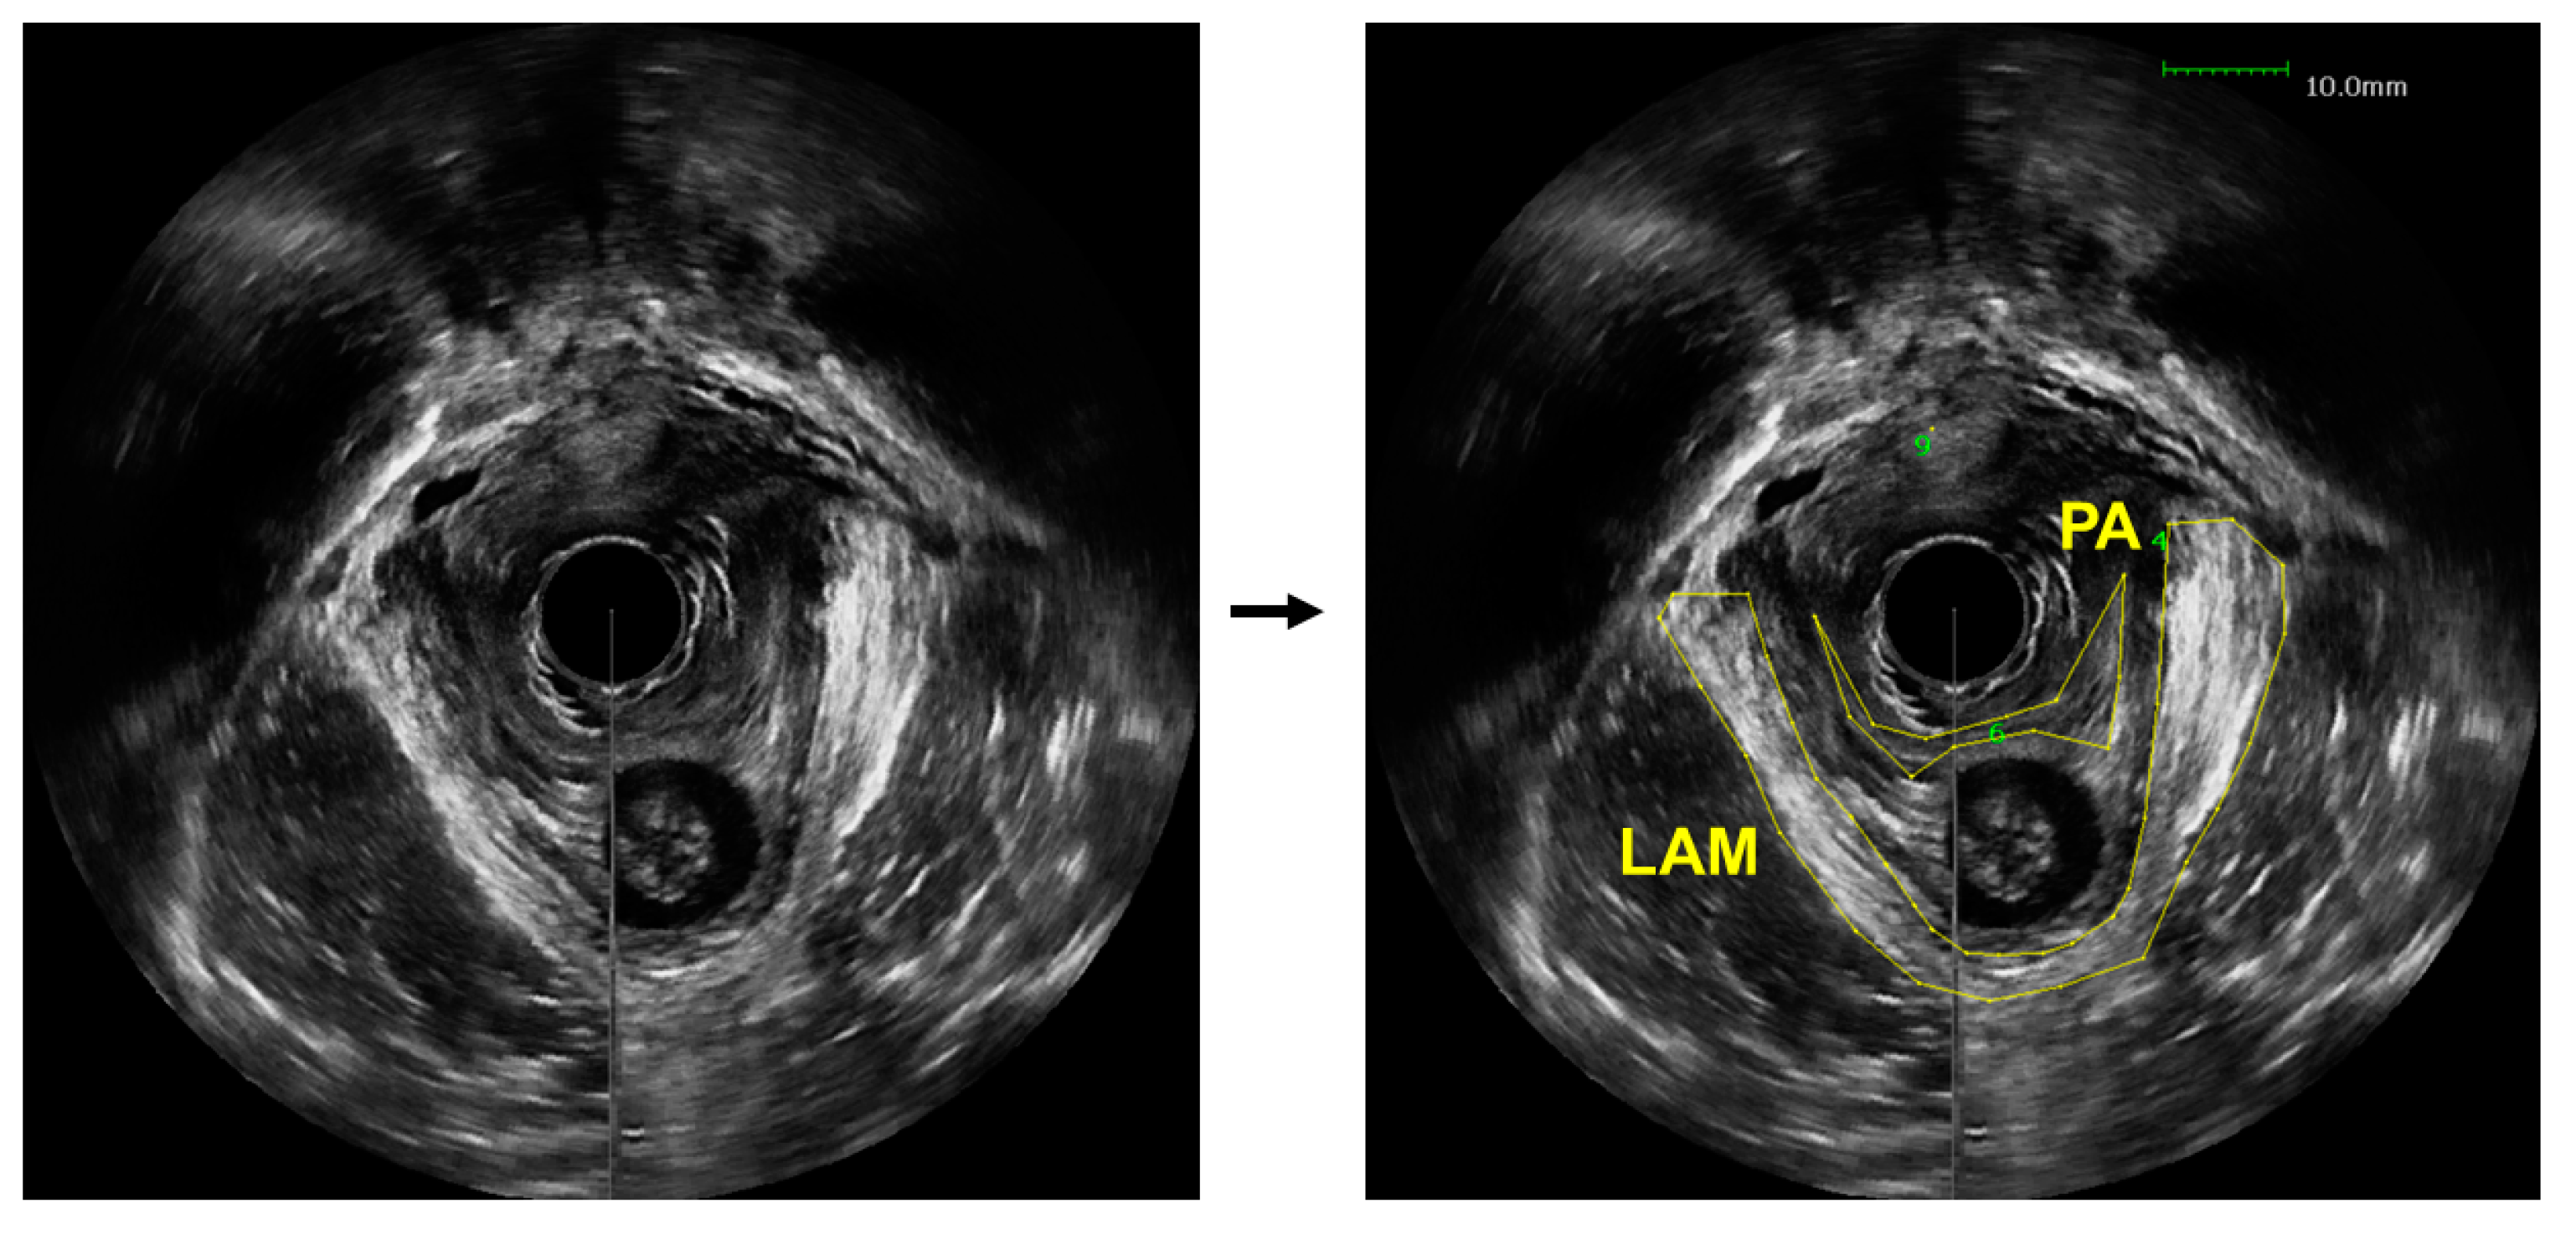

Figure 1.

An axial view image obtained from a 3D endovaginal ultrasound image acquired from a patient with pelvic floor prolapse (left). Levator ani muscle (LAM) and puboanalis (PA) were traced by an urogynecologist using the BK viewer software (right).